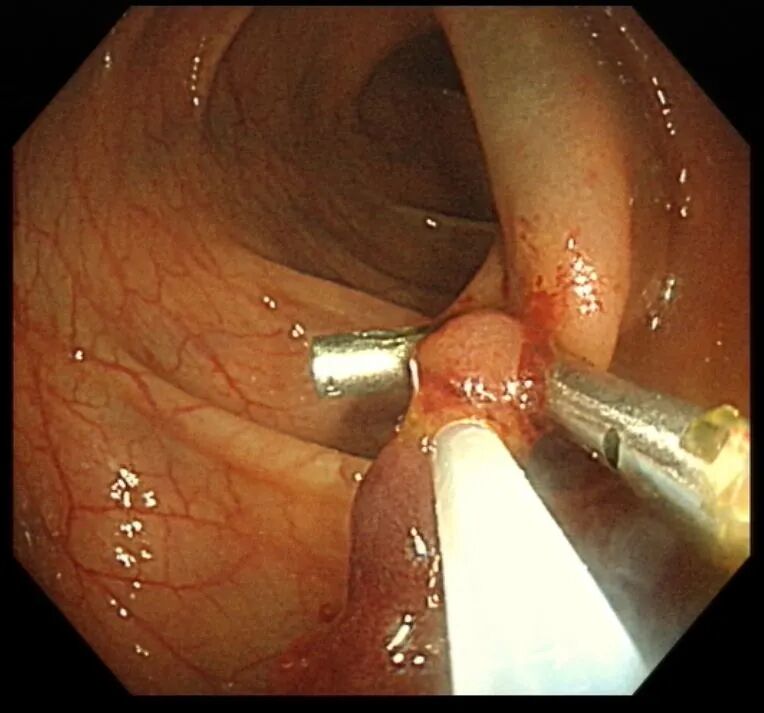

考虑到息肉体积大、蒂部粗壮,内部极可能存在粗大的滋养血管,直接切除极易引发术中、术后出血,徐思楠医生当机立断,在和小金妈妈充分沟通、取得书面知情同意后,当场为小金制定了缜密的手术方案,在手术过程中,徐医生先用数枚钛夹精准夹闭息肉的粗蒂根部,彻底阻断息肉的血液供应,再用圈套器完整套住息肉头部,通过规范的电凝电切操作将息肉完整切除,最后再用钛夹严密封闭手术创面,全程几乎无明显出血,操作顺利完成。术后,小金转入住院部,接受了规范的禁食、静脉补液、营养支持等治疗,未出现出血、穿孔等并发症,很快恢复了正常饮食,顺利康复出院。术后病理结果最终揭晓,这枚息肉为幼年性息肉,属于良性病变,后续只需定期复查肠镜即可。